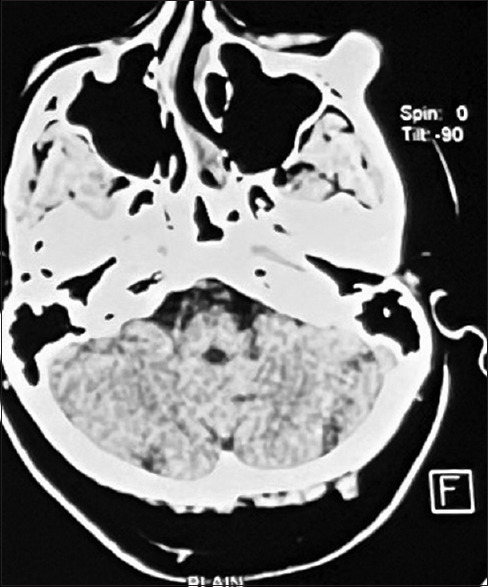

Rationale: Osteochondroma, a benign bony neoplasm that can develop in any part of the body, commonly appears in the ends of the long bones. It can also occur in the craniofacial region such as mandibular condyle and coronoid region. We describe the clinical presentation, diagnostic process, surgical management and post-operative outcomes in a 34-year-old male patient. Only few cases are reported in literature till now and often are mistaken as bony exostosis.

Diagnosis: Through clinical palpation and radiological interpretation. Provisional diagnosis of bony exostosis was made, which was later confirmed as osteochondroma on histopathological examination.